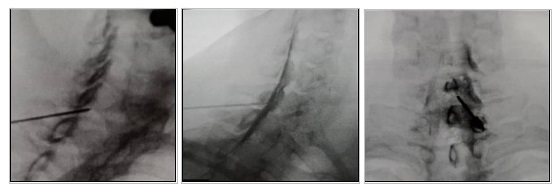

Τι είναι η αυχενική επισκληρίδιος έγχυση

Η αυχενική επισκληρίδιος έγχυση αποτελεί μια ελάχιστη επεμβατική πράξη, η οποία συνίσταται σε έγχυση τοπικού αναισθητικού και κορτιζόνης στον επισκληρίδιο χώρο της αυχενικής μοίρας της σπονδυλικής στήλης. Η κορτιζόνη ασκεί ισχυρή αποιδηματική και αντιφλεγμονώδη δράση πάνω στα αυχενικά νεύρα, ανακουφίζοντας σαφώς τον πόνο. Η θεραπευτική παρέμβαση διενεργείται στο χώρο του χειρουργείου, υπό τοπική αναισθησία και κάτω από συνεχή ακτινοσκοπική καθοδήγηση.

Πώς γίνεται η αυχενική επισκληρίδιος έγχυση

Ο ασθενής ξαπλώνει μπρούμυτα, ένα μαξιλάρι τοποθετείται κάτω από το στήθος του ασθενούς και ο αυχένας λυγίζει ελαφρά με το μέτωπο να ακουμπά στο κρεβάτι. Το δέρμα αποστειρώνεται πλήρως και ένα διάλυμα τοπικού αναισθητικού χρησιμοποιείται για να μουδιάσει το δέρμα. H βελόνα παρακέντησης εισάγεται στο κατώτερο αυχενικό ή στο πρώτο θωρακικό μεσοσπονδύλιο διάστημα και εισέρχεται σταδιακά κάτω από συνεχή ακτινοσκοπικό έλεγχο στον επισκληρίδιο χώρο. Μέσω της βελόνας παρακέντησης προωθείται ένας πολύ λεπτός καθετήρας στον επισκληρίδιο χώρο, μέσω του οποίου εισάγεται η σκιαγραφική ουσία σε πρώτο χρόνο και το θεραπευτικό διάλυμα σε δεύτερο χρόνο. Ο καθετήρας και η βελόνα αφαιρούνται προσεκτικά και τοποθετείται μία μικρή αυτοκόλλητη γάζα στο σημείο παρακέντησης.